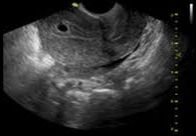

ECOGRAFIAS

GI-RADS: GYNECOLOGIC IMAGING REPORTING AND DATA SYSTEM. ES LA CLASIFICACIÓN PARA EL INFORME ECOGRÁFICO DE LAS IMÁGENES ANEXIALES ( DE LOS OVARIOS Y TROMPAS DE FALOPIO) [...]